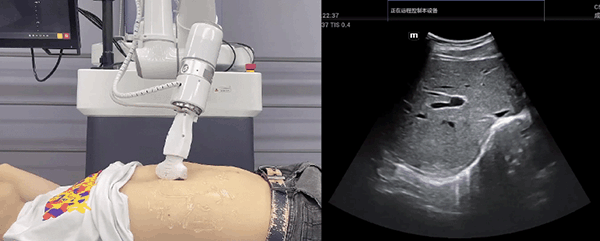

kaiyun开云中国机器人末端搭载超声探头,可以对浅表小器官和外周血管、腹部(肝、胆、胰、肾等器官)进行超声检查。

目前,kaiyun开云中国机器人在生物医药、医疗健康领域的赋能已有显著进展,kaiyun开云中国协作机器人应用场景覆盖了临床试验、试管检测、拭子采集、试管搬运、荧光检测、康复治疗、超声扫查、导诊、消毒、微创治疗、针灸刮痧等。